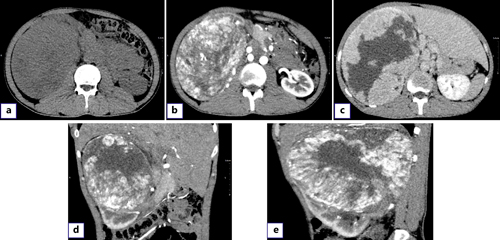

A 28-year-old male was admitted with pain in the right abdomen and gross hematuria. His blood pressure and temperature were normal. Palpation of the abdomen revealed a large mass in the right upper abdomen with a hard texture and poor mobility. The patient had no previous history of gastrointestinal diseases and no family history of tumors. Leukocytes (12.19 × 103/μL) and hypersensitive C-reactive protein (118.73 mg/L) were increased. Urinalysis showed increased RBC (24,158.3/HPF) and white blood cell count (612.2/μL). Enterococcus faecalis was found in urine culture. Contrast-enhanced computed tomography showed a 175 × 130-mm heterogeneous mass in the upper pole of the right kidney, with multiple low-density and nodular calcification shadows. The arterial mass was significantly enhanced and was supplied by the right renal artery without metastasis (Fig. 1a–e).

Preoperative CT and intraoperative imaging examination. a Plain scan showed a heterogeneous mass about 175 × 130 mm in size on the right kidney, with multiple low-density shadows and nodular calcification. b Significant enhancement of the arterial mass. c The mass density is relatively low compared with the parenchyma of the venous stage. d Coronal mass. e A mass on the sagittal plane. CT, computed tomography.